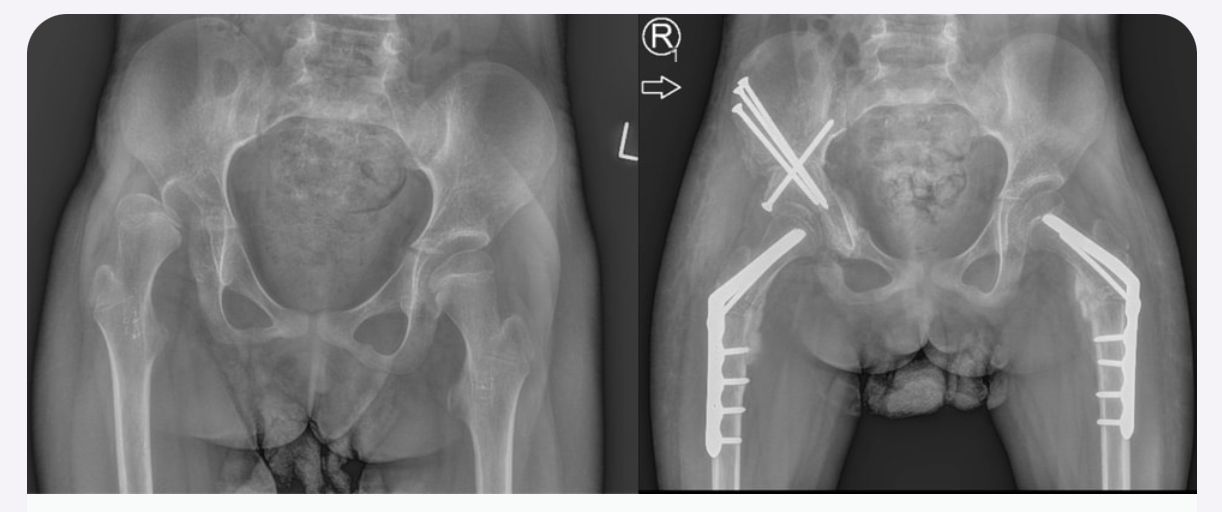

Jestem chirurgiem specjalizującym się w zaawansowanych rekonstrukcjach stawów oraz wydłużaniu kończyn dolnych (limb lengthening and reconstruction surgery). Kompleksowo opiekuję się osobami z problemami o podłożu ortopedycznym oraz neurologicznym, szczególnie dzieci z wadami wrodzonymi i schorzeniami nerwowo-mięśniowymi. Dzięki wieloletniemu doświadczeniu w nowoczesnych technikach rekonstrukcyjnych znacząco udoskonaliłem metody chirurgicznego leczenia dzieci z problemami neurologicznymi, otwierając przed nimi nowe możliwości poprawy funkcjonalności oraz jakości życia. Specjalizujemy się w jednoczasowych wielopoziomowych rekonstrukcjach kończyn (SEMLS) oraz kompleksowych rekonstrukcjach stawów biodrowych, łącząc sprawdzone techniki operacyjne z innowacyjnymi rozwiązaniami. Oprócz leczenia operacyjnego, koordynuje leczenie zachowawcze, obejmujące wielopoziomowe podania toksyny botulinowej (BTX) oraz minimalnie inwazyjne procedury, takie jak SPML (Selective Percutaneous Myofascial Lengthening) czy PERCS (Percutaneous Muscle Lengthening). Każdy pacjent otrzymuje indywidualnie opracowany program terapeutyczny, którego celem jest osiągnięcie najlepszych efektów przy minimalnym obciążeniu. Opiekuję się również pacjentami dorosłymi wymagającymi endopiotezoplastyki stawów oraz ratowaniem kończyn przed amputacją z powodu aktywnej lub przewlekłej infekcji W mojej pracy kluczowe jest podejście holistyczne, które łączy zaawansowane techniki chirurgiczne z terapią zachowawczą, aby zapewnić pacjentom kompleksową opiekę oraz trwałe efekty leczenia. Powierzenie nam zdrowia pacjentów jest dla nas ogromną odpowiedzialnością, a jednocześnie najwyższym zaszczytem. Zakres mojej specjalizacji obejmuje leczenie: 1. Wady wrodzone i rozwojowe kończyn: Hemimelia strzałkowa, niedorozwój kości udowej (CFD – Congenital Femoral Deficiency) – zaawansowane metody rekonstrukcyjne, w tym wydłużanie oraz procedury typu SUPERhip, SUPERankle Brak kości promieniowej i inne deformacje kończyny górnej – zabiegi ulnaryzacji, pollicyzacji, korekcji osi Mnogie wyrośla chrzęstno-kostne (MHE) – chirurgiczna korekcja deformacji i zapobieganie wtórnym ograniczeniom ruchomości Wrodzony staw rzekomy kości piszczelowej (CPT) – rekonstrukcja podudzia metodą CPT Xunion 2. Zaburzenia osi i długości kończyn: Skrócenia kończyn – techniki wydłużania z zastosowaniem gwoździ teleskopowych, aparatów Ilizarowa oraz STRYDE i PRECICE Zaburzenia osi kończyn (koślawość, szpotawość, rotacje) – korekcje wielopłaszczyznowe, osteotomie oraz stabilizacja z użyciem aparatów zewnętrznych i gwoździ wewnętrznych 3. Neuroortopedia – leczenie pacjentów z zaburzeniami neurologicznymi: Mózgowe porażenie dziecięce (MPD) – operacje zmniejszające spastyczność, korekcje stawów oraz zabiegi wielopoziomowe poprawiające funkcję chodu Przepuklina oponowo-rdzeniowa (spina bifida) – leczenie deformacji stóp i kończyn dolnych, stabilizacja stawów Artrogrypoza – wieloetapowe leczenie chirurgiczne poprawiające zakres ruchu i funkcjonalność kończyn 4. Zakażenia i zaburzenia zrostu kostnego: Osteomyelitis (zakażenia kości i szpiku) – leczenie chirurgiczne i antybiotykoterapia celowana Zaburzenia zrostu kostnego, brak zrostu (non-union, mal-union) – nowoczesne techniki transportu kostnego, przeszczepów i stabilizacji 5. Rekonstrukcja dużych stawów i leczenie deformacji: Endoprotezoplastyka biodra, kolana i stawu skokowego – zarówno w przypadkach zwyrodnieniowych, jak i pourazowych Choroba Legg-Calvé-Perthesa – metody operacyjne poprawiające ukrwienie głowy kości udowej i ograniczające deformację Złuszczenie głowy kości udowej (SCFE – Slipped Capital Femoral Epiphysis) – leczenie za pomocą zmodyfikowanej metody Dunna, pozwalającej na anatomiczną rekonstrukcję biodra i zachowanie funkcji stawu Dysplazje szkieletowe – interdyscyplinarne podejście do leczenia deformacji i ograniczeń funkcjonalnych 6. Leczenie stopy cukrzycowej i deformacji stóp: Stopa cukrzycowa – nowoczesne techniki rekonstrukcji stopy, zapobieganie amputacji Deformacje stopy (np. stopa końsko-szpotawa, płasko-koślawa, stopa sierpowata) – korekcja chirurgiczna i indywidualne podejście do biomechaniki chodu 7. Chirurgia urazowa dzieci i dorosłych: Leczenie złamań z zastosowaniem minimalnie inwazyjnych technik operacyjnych Rekonstrukcja kończyn po urazach, w tym ratowanie kończyny zagrożonej amputacją Stabilizacja wewnętrzna i zewnętrzna złamań patologicznych oraz pourazowych 8. Osseointegracja - zaopatrzenie pacjentów po amputacji poprzez korekcję kikuta lub aplikację osseointegracji do kości powyżej lub poniżej kolana wraz z zaopatrzeniem prtotetycznym 9. Wydłużanie kosmetyczne kończyn dolnych i górnych. Wykonujemy jednoczasowe operacje zarówno wydłużania kości udowych i piszczelowych jako jedyny ośrodek w Europie. Efekt jaki możemy uzyskać to 10-12 cm zwiększenia wzrostu. Wierzę, że najlepsze efekty leczenia można osiągnąć dzięki współpracy grona specjalistów, kierując się zasadą pacjentocentryzmu, która stawia potrzeby pacjenta w centrum procesu terapeutycznego.. Dlatego każda konsultacja odbywa się w interdyscyplinarnym zespole, w skład którego wchodzą ortopedzi, fizjoterapeuci, ortotycy i terapeuci zajęciowi. Pierwsza wizyta trwa około 1,5 godziny i obejmuje szczegółową ocenę stanu zdrowia oraz opracowanie planu leczenia chirurgicznego. W naszym instytucie działamy na podstawie indywidualnie opracowanych dla każdej jednostki chorobowej protokołów leczenia operacyjnego oraz postępowania fizjoterapeutycznego, których jestem współautorem. Dzięki temu zapewniamy spójne, kompleksowe i skuteczne podejście terapeutyczne, dostosowane do specyfiki danej choroby i indywidualnych potrzeb pacjenta. Zapraszam na konsultacje ortopedyczne, neuroortopedyczne oraz deformacyjne.